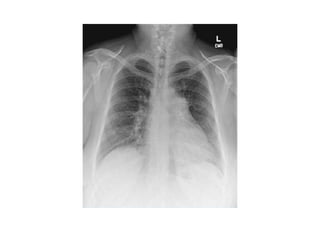

Chest radiograph shows silhouette sign, with

obscuration of right border of heart (arrows).

Lingular segment consolidation

Chest radiograph showssilhouette sign, with obscuration of right border of heart (arrows).